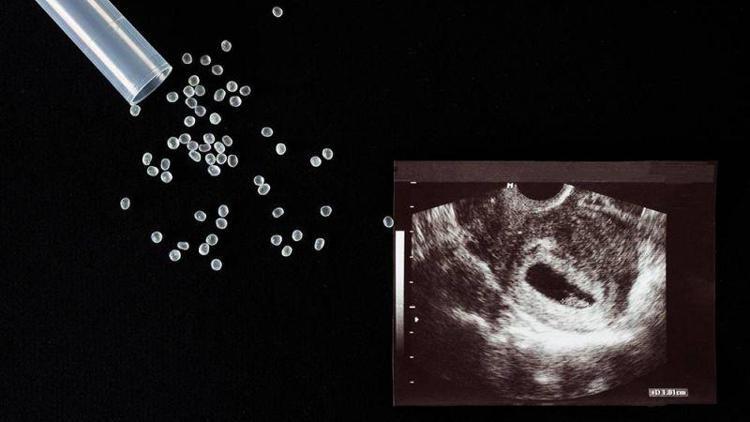

Erken Menopoz yaşayan ya da kötü kaliteli embriyolara sahip olduğundan ötürü gebelik elde edemeyen kadınlar için gebelik mümkün değildir. Bu hastaların başvurabileceği tek yöntem ise “Yumurta bağışı” olarak görülür. Kadınlarda 45 yaşından sonra bir mucize olarak görülen gebelik, yumurta bağışı ile birlikte ikiz bebek doğumlarını dahi mümkün kılabilir.

YUMURTA BAĞIŞI YÖNTEMİ İLE GEBELİK NASIL GERÇEKLEŞİR?

- Bu yöntemle gebelik elde etmek isteyen kadınlar için ilk olarak genç bir verici bulunur.

- Vericiden alınan yumurtalarla, alıcının eşinin spermleri döllendirilir ve alıcının rahimine yerleştirilir.

- Genetik açıdan verici kadının özelliklerini taşıyan yumurtalar, doğal olarak doğacak bebeğin de eş ve vericiye ait genetik özelliklere sahip olmasına neden olmaktadır.